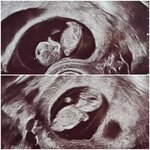

Minizwerge 👶👶

Wir freuen uns, dass ihr unseren kleinen Minizwergen 💙💗eine Freude machen wollt 🥰 das ist wirklich toll, darüber freuen wir uns total